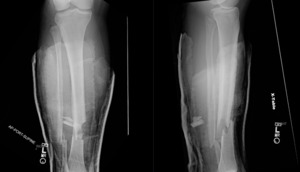

The patient involved in this case was a 23-year old male with no previous past medical history. He was brought to the emergency department via ambulance after a motorcycle crash during which he was struck by a car traveling roughly 60 miles per hour. The patient stated that he flipped over the bike and landed on his right leg with immediate pain, deformity, and bleeding. In the emergency department he was found to have an open right tibia fracture, at which time the orthopedics department was consulted. Two wounds were identified over the anterior aspect of the midshaft of the tibia. An additional open wound was identified over the posterior aspect of the tibia measuring approximately 1 cm x 5 cm in the horizontal direction. Patient was noted to have deficits in sensation and motor in the common peroneal nerve (CPN) distribution with 3/5 motor and 1/2 sensation responses. Dorsalis pedis and posterior tibial pulses were palpated and 2+ with cap refill less than 2 seconds. The compartments remained compressible and pain was well controlled. Imaging following reduction and immobilization demonstrated displaced distal one-third shaft fractures of the tibia and fibula (Fig. 1, Fig, 2).